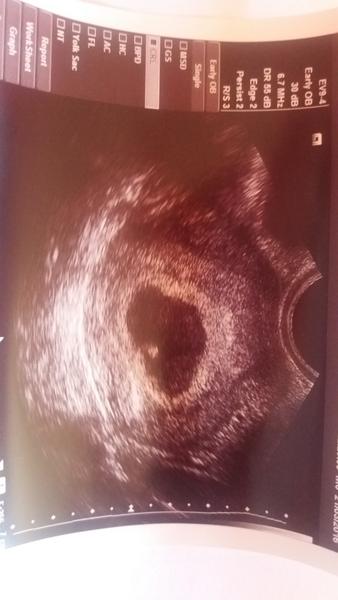

Ahoj holky. Volám sa Bara a chtěla sem se zeptat či nevíte mi poradit.dnes sem 7+3 ale podle uz5+5.dr v Cb má poslal na gyndu že je to ZT ale u nás ještě čekají proto že je patrna pulzace. Hcg mam 1740 stoupa pomalu.jsem po IUI. Díky

Jak to tu ctu, tak jsem nervozni. vsechny jste skoro uz v 6tt videly plod. ja byla včera na utz 5+4tt a jen 10mm gestacni vacek a nic v nem,ani zloutkovy vacek ☹

Ja plod nevidela v 5tt to by jen vacek a v tom 6tt tam byl vacek a bylo tam nekde srdicko, ale plod jsem nevidela. Nebojte se, bude to oki

U me treba doktorce nevychazely tydny podle menstruace protoze to male bylo velike na to kolik by mu opravdu melo byt tt, takze to brala tak nejak odhadem. V kazdem to miminko roste jinak bych rekla. nebojte se, to prijde, jen tomu malemu dejte cas 🙂

no, ale už na tom UTZ jde vidět, že v té dutince něco je. Já ji měla úplně prázdnou. Uvidíme co v pondělí. Snad se nějak prcek ukáže. Pořád doufám v to, že třeba ten ultrazvuk v nemocnici na vinohradech nebyl úplně nejnovější a že tam třeba 2mm semínko prostě nešlo zobrazit. Pořád doufám, že tam je. Akorát mi ze dne na den zmizely všechny příznaky, které jsem měla a ještě se nic nevrátilo :(